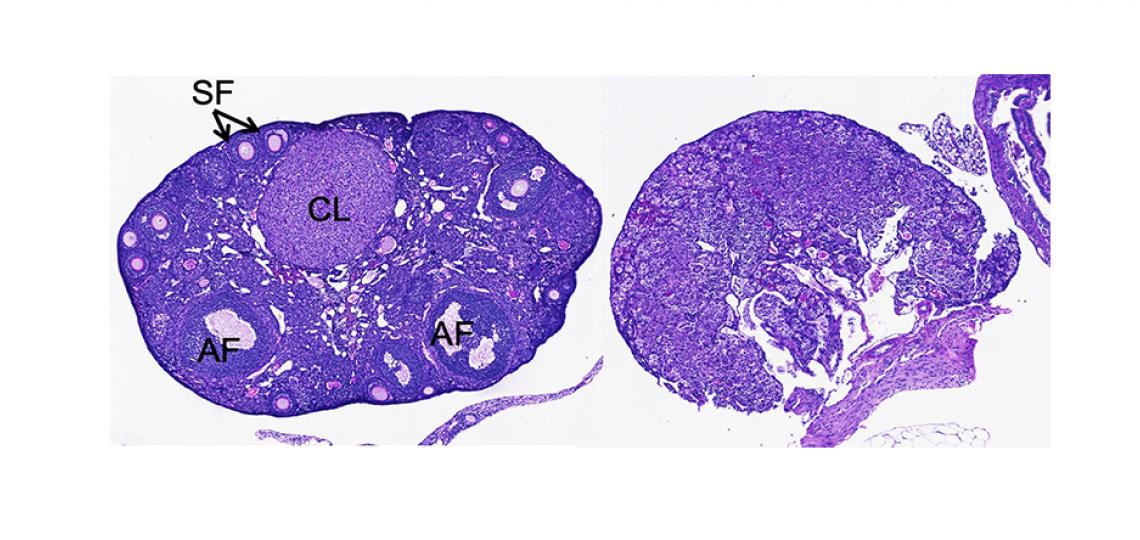

Images from Larina Laboratory

Figure 1: Individual sperm tracking (colored line) toward ovulated eggs within in the mouse oviduct captured in vivo with optical coherence tomography. Image from Shang Wang, PhD, a postdoctoral fellow in the Larina Laboratory.

Figure 2: The mouse female reproduction system imaged with microcomputed tomography (micro-CT) Image by Zheng-Chen Yao in the Larina Lab